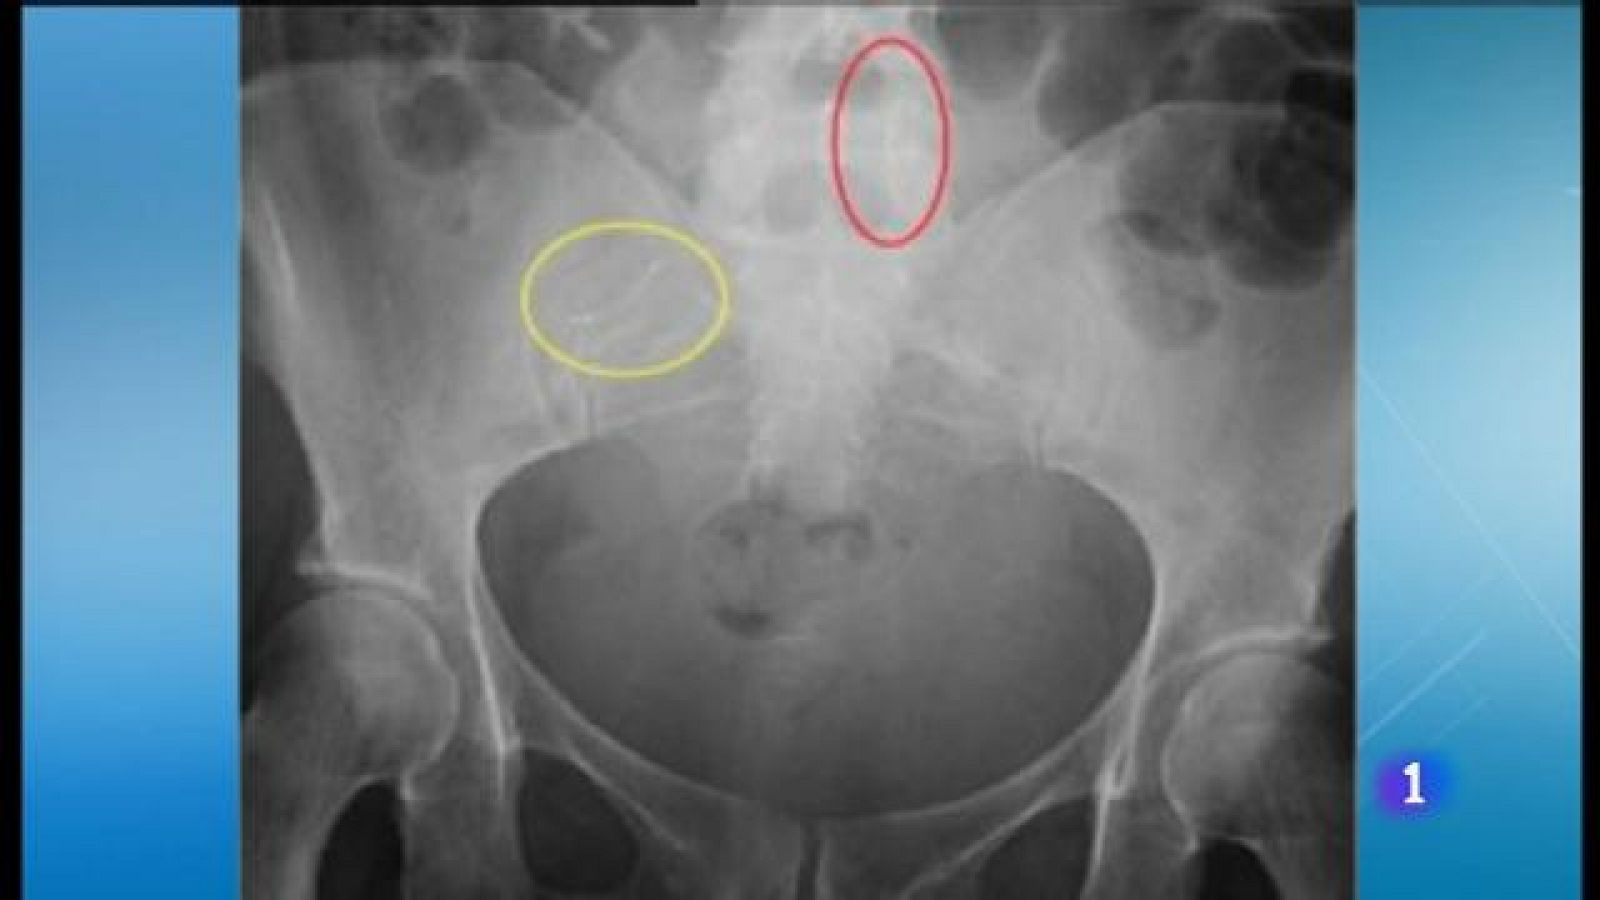

Cinc dones preparen una demanda contra l'Ib-Salut per les seqüeles que han patit després de la implantació de l'Essure. Bayer va retirar-lo del mercat l'any passat, quan la seva seguretat ja era qüestionada.